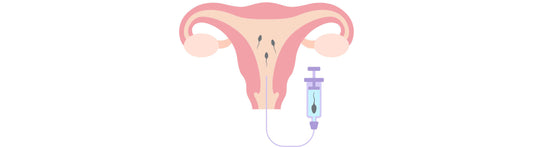

When trying to conceive, couples may explore different options, including at-home insemination. At-home insemination involves the introduction of semen into the female reproductive system outside of sexual intercourse. This process...

When trying to conceive, couples may explore different options, including at-home insemination. At-home insemination involves the introduction of semen into the female reproductive system outside of sexual intercourse. This process...

Assisted reproductive technologies have come a long way in helping couples conceive. Intrauterine insemination (IUI) and intracervical insemination (ICI) are two of the most commonly used techniques to help couples...

Assisted reproductive technologies have come a long way in helping couples conceive. Intrauterine insemination (IUI) and intracervical insemination (ICI) are two of the most commonly used techniques to help couples...

Embarking on the journey of conception can be a transformative experience, and for those exploring self-insemination, it's crucial to understand the methods and tools available. One such method involves the...

Embarking on the journey of conception can be a transformative experience, and for those exploring self-insemination, it's crucial to understand the methods and tools available. One such method involves the...